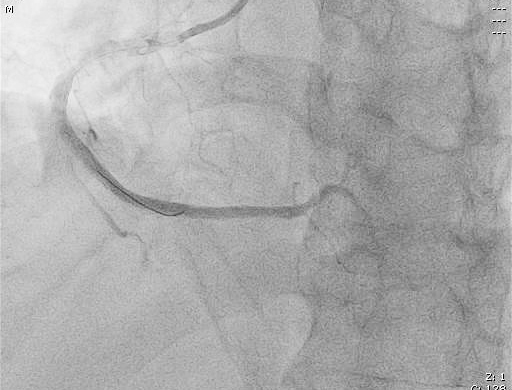

患者進(jìn)入導(dǎo)管室后,憋喘明顯,血壓、氧飽和度低,需面罩吸氧、大劑量去甲腎上腺素維持血壓。朱宗濤主任建議應(yīng)使用強(qiáng)支撐指引導(dǎo)管,先用軟導(dǎo)絲輕柔操作,結(jié)合血管內(nèi)超聲(IVUS),嘗試尋找血管真腔。術(shù)中選擇6F SAL指引導(dǎo)管行冠狀動(dòng)脈造影提示右冠中段閉塞,先后嘗試Anyreach、Sion工作導(dǎo)絲未能通過閉塞病變,然后在Finecross微導(dǎo)管輔助下,換用Gaia1硬導(dǎo)絲通過閉塞處成功送至右冠遠(yuǎn)端,行血管內(nèi)超聲(IVUS)檢查顯示血管支架遠(yuǎn)段局部夾層、血腫,導(dǎo)絲全程位于血管真腔,在IVUS精確定位下,成功開通血管并植入支架2枚。術(shù)后,經(jīng)CCU醫(yī)護(hù)人員的精心治療,已于10月10日康復(fù)出院。

術(shù)后